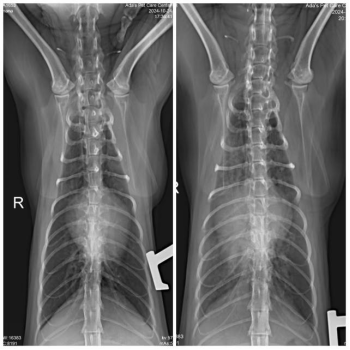

First, we conducted a chest X-ray, which revealed diffuse increased density in the lungs, potentially indicating fluid accumulation, and suggesting a possible heart issue. Additionally, the X-ray showed bronchial signs and an unclear heart silhouette, hinting that the heart might be enlarged or have other abnormalities.